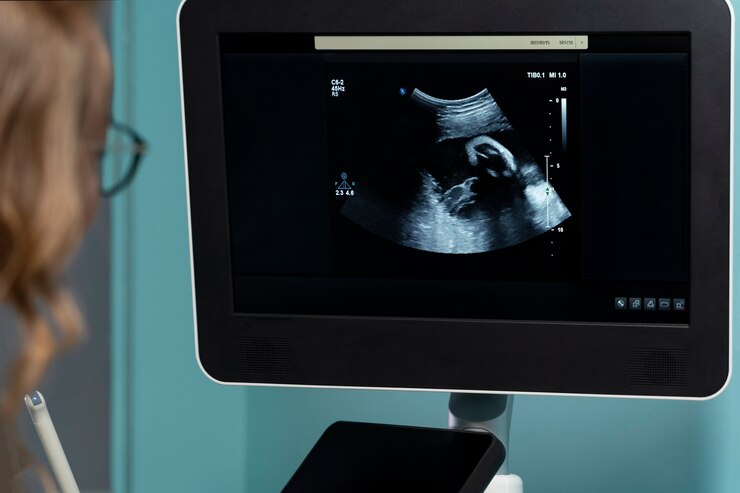

Сканер УЗИ Mindray MX7 широко применяется как в диагностике, так и в оперативном вмешательстве. Он является надежным помощником врачей различных специальностей, обеспечивая точные и качественные результаты исследований. Наиболее часто данный сканер используется при обследовании женщин в период беременности, поскольку он позволяет осуществлять ультразвуковой контроль развития плода, а также обнаруживать любые патологии или аномалии в структуре органов малыша.

Одним из ключевых направлений применения сканера УЗИ Mindray MX7 является акушерство и гинекология. С помощью этого устройства можно проводить всестороннюю оценку состояния матки, яичников, плода и плодных оболочек. Благодаря высокому разрешению изображения и режиму Doppler, врачи получают детальную информацию о кровотоке, что позволяет диагностировать различные патологии и контролировать развитие беременности.